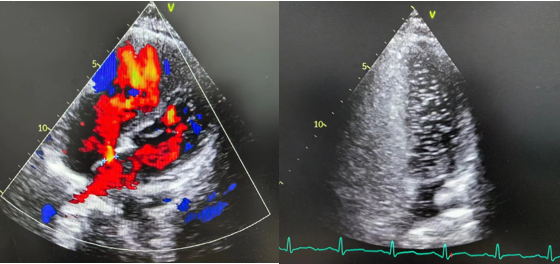

▲超声心动图和右心声学造影(发泡试验)

经心血管科会诊后行食道超声心动图检查+右心声学造影,证实为卵圆孔未闭(分流量3级)。